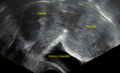

A very large (9 cm) fibroid of the uterus which is causing pelvic congestion syndrome as seen on ultrasound

A small uterine fibroid seen within the wall of the myometrium on a cross-sectional ultrasound view